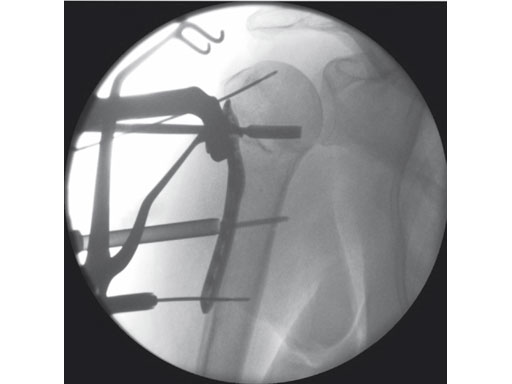

The 3.5 mm LCP percutaneous aiming system for PHILOS offers the possibility to insert the PHILOS plate through the transdeltoid approach and to insert the shaft screws percutaneously enabling a less-invasive application of PHILOS.

The system consists of a sleeve system and an aiming arm. It is used analogously to the existing PHILOS aiming instruments and other aiming systems. The aiming arm is radiolucent to allow control under image intensifier. Locking as well as cortex screws can be used through the device. Compression achieved by cortex screws in the shaft may lead to plate tension. The device has to be locked to the plate at both ends to ensure the plate-device alignment.

A safe zone is defined to protect the axillary nerve (screw holes near the axillary nerve are not accessible through the device). Therefore, the elongated plate hole is not accessible through the aiming arm due to the protected nerve zone. However, by abduction of the arm after fixation, these screw holes become accessible.